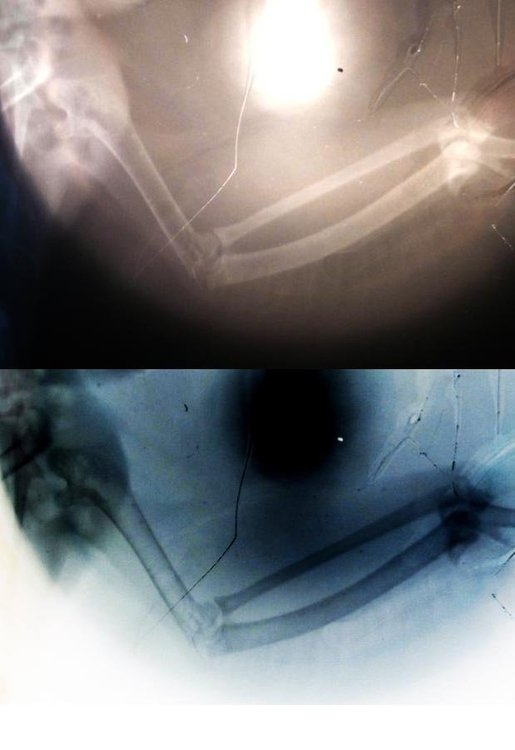

Zosia Опубликовано 25 апреля, 2019 #46 Опубликовано 25 апреля, 2019 вот поиграла в фотошопе- все видно хорошо

Demonit Опубликовано 26 апреля, 2019 Автор #66 Опубликовано 26 апреля, 2019 Если пальчик отомрёт - насколько это плохо? Подозреваю, что лечение нужно начать как можно быстрее, но судя по всему оно начнется только завтра. Нашел только пару мест, где одновременно можно купить Травматин и Артрогликан, и то о точном наличии можно будет узнать только завтра (я сам администратор интернет-магазина и знаю, что отображение фактического наличия - это сильно дорого). Пока решаю вопрос с "человеческими" препаратами, утолите любопытство) 22 часа назад, Zosia сказал: вот поиграла в фотошопе- все видно хорошо Где видно?) Возможно мне даже как-то поможет в реабилитации.